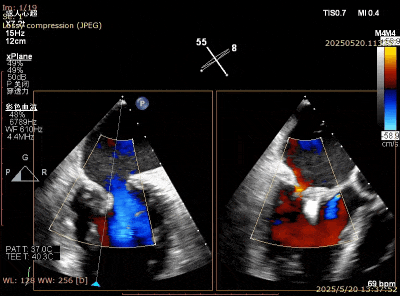

在经股静脉途径的TEER手术时,房间隔穿刺是一个很重要的基础步骤。有时候房间隔组织较韧较厚(多见于房间隔短穿刺位置需要靠后,或者外科房间隔修补术后),穿刺针通过之后要通过导引大鞘(GC)存在着较大困难,若强行推送大鞘可引起房间隔撕裂到左心房顶引起灾难性心包填塞。传统做法时使用外周球囊对房间隔进行扩张,但是不是每个导管室都常规配备外周球囊,且使用过大球囊仍可引起房间隔撕裂风险。我们提供了一种更简洁的方式,即使用导引鞘内芯和房间隔穿刺鞘两个管子(双管齐下)同时扩张房间隔穿刺口,再推送导引大鞘通过房间隔,无需额外器械,操作简单高效且安全(图1-4)。

图1. 房间隔穿刺处肥厚,GC难以通过房间隔